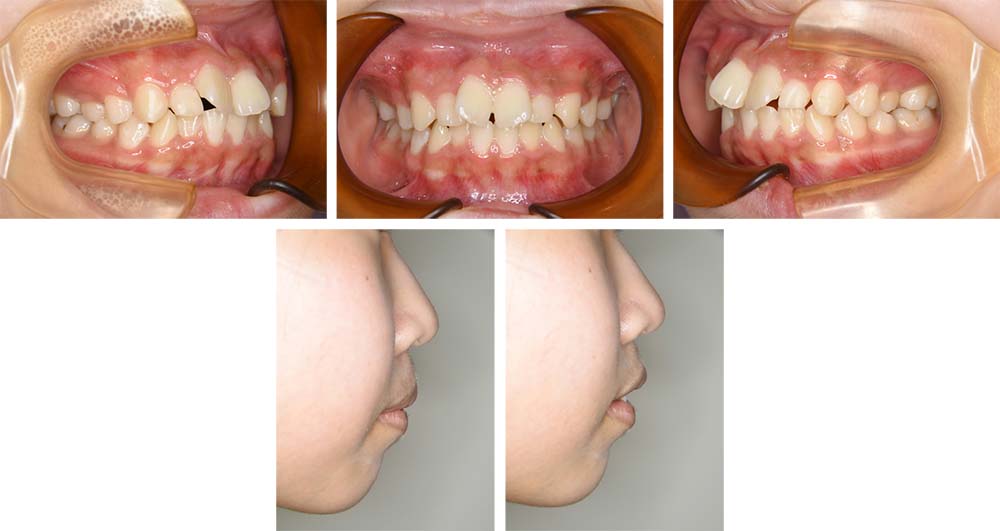

上顎前歯のねじれと前歯の前突を主訴に来院された。口元の突出があり、セファログラムの分析を基に前歯部叢生を伴う上下顎前突と診断し、上下顎前歯を整え後退を行うことを治療目標とした。側方歯の交換期に入っていたことから、永久歯への生え代わりを待ち、13歳まで経過観察を行った。永久歯への生え代わりが終了し、下顎第二大臼歯の萌出を認めたことから、上下顎小臼歯を抜歯していただき前歯を後退させるために上下顎唇側マルチブラケット装置を使用して動的治療を行った。矯正用ゴムの使用やブラッシングなど協力状態も極めて良く、前歯が適正な状態に後退して、上口唇がE-ラインから2㎜程度、下口唇はE-ライン上にそれぞれ後退し、美しいオトガイ形態となって口元の安寧を得ることができた。臼歯部の咬合状態も良好な状態であった。動的治療期間2年2か月間。

初診時

治療前

治療後